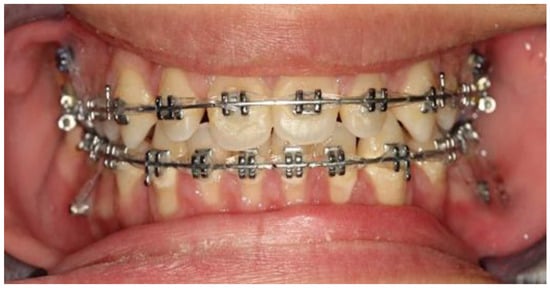

3. Results